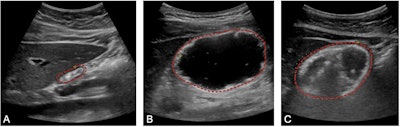

Representative images obtained during this study illustrating an empty (A) gastric antrum (outlined in red), one filled with liquid (B), and one filled with solid food components (C). Images available for republishing under Creative Commons license (CC BY 4.0).Journal of Clinical Anesthesia